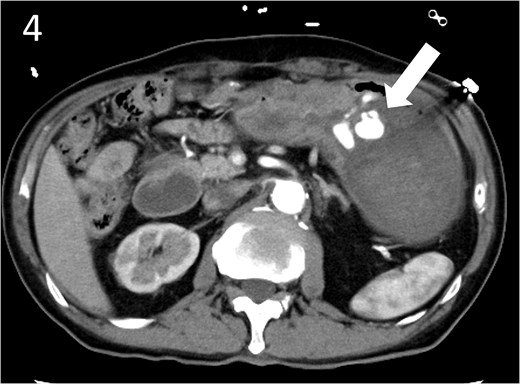

Contrast-enhanced computed tomography image showing active contrast extravasation in the stomach (arrow).

A 78-year-old man was transferred to our hospital because of hypovolemic shock. He had already received 10 units of RBC concentrate. His blood pressure was 97/64 mmHg. The patient’s haemoglobin level was 8.2 g/dL. Contrast-enhanced CT showed active contrast extravasation in the stomach (Fig. 4). Emergency angiography revealed tumour staining in both the left and right gastroepiploic arteries, which were coil embolized (Fig. 5). Upper GI endoscopy 2 days later revealed a type 4 tumour without bleeding (Fig. 6). The patient was diagnosed with resectable GC, and underwent laparoscopic total gastrectomy with Roux-en-Y reconstruction and lymph node dissection. The final histopathological diagnosis was T4aN3aM0 stage IIIC. Macroscopic findings revealed a type 4 tumour of the stomach, and histopathological findings revealed that the tumour was a poorly differentiated adenocarcinoma with squamous cell differentiation. All surgical margins were negative. The patient developed a minor leakage that resolved spontaneously. The patient has remained recurrence-free for 12 months.